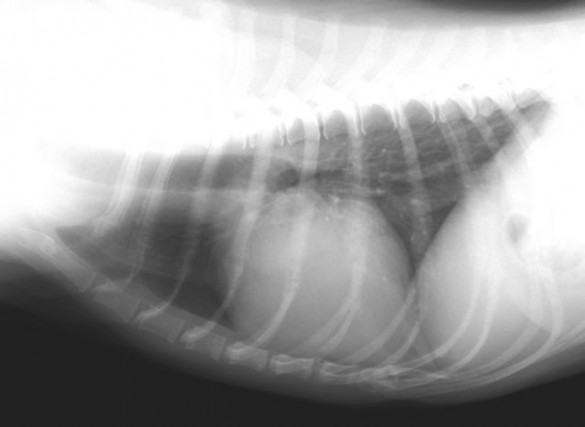

腫瘤発見時のレントゲン写真

肺内尾側(画面上黒い部分の右側)に腫瘤陰影が認められる。